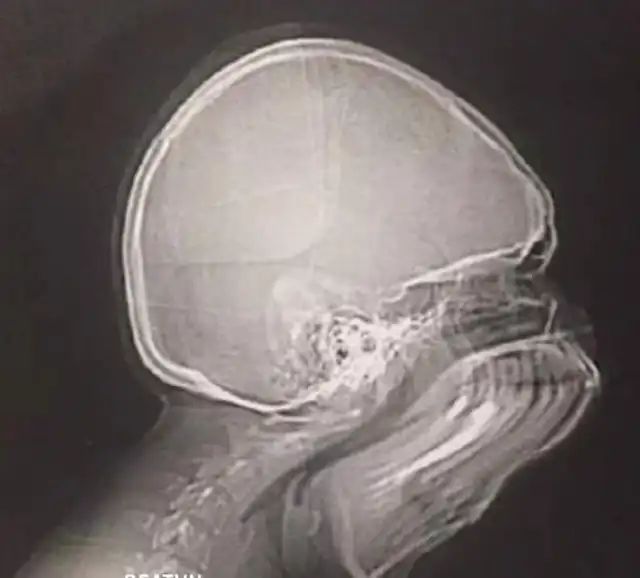

Как будет выглядеть рентген, если вы чихнете в самый неподходящий момент

Вот так, как на этом фото, выглядит обычный рентген. А вы когда-то задумывались над тем, как будет выглядеть рентген, если пациент случайно чихнет во время создания снимка? Хотите взглянуть на то, что из этого вышло? Тогда смотрим.